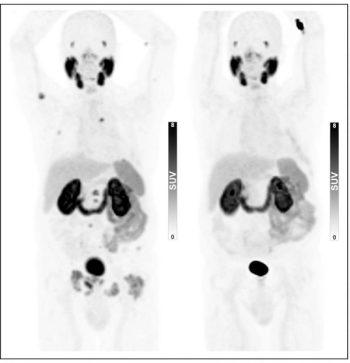

For patients 80 years of age or older that have a PSA level at 20 ng/mL or higher, PSMA PET/CT has a high likelihood of success in diagnosing and staging prostate cancer regardless of pre-imaging biopsy use, according to newly published research.